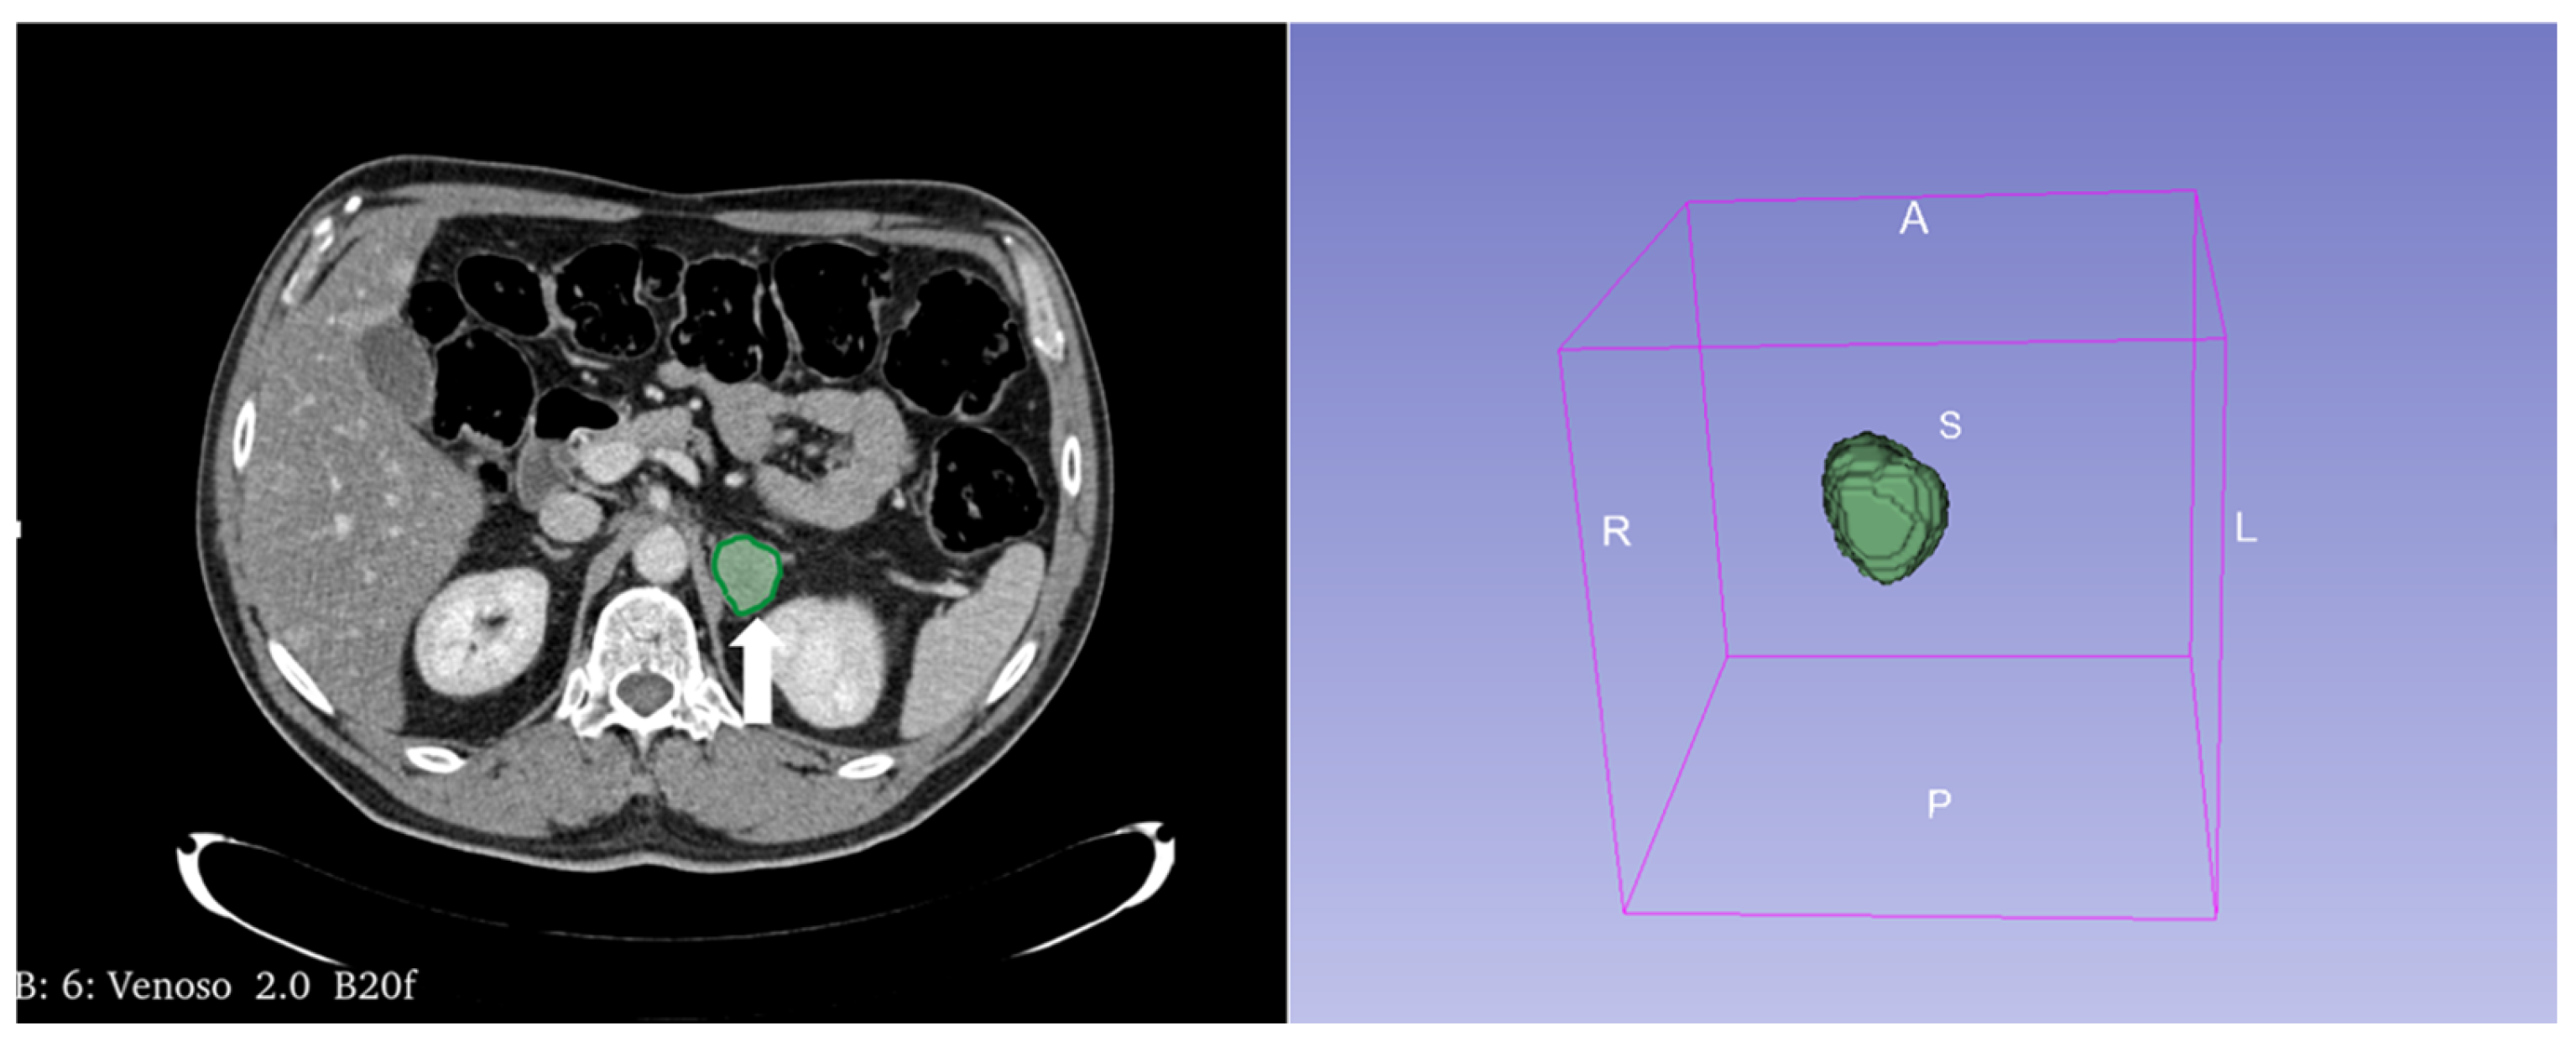

Figure 13.

An example of segmentation of an LPA in the right adrenal gland (arrow) in an unenhanced CT phase using 3D Slicer software (version 4.11). The volume of interest (VOI) of the LPA was manually drawn covering the whole lesion.